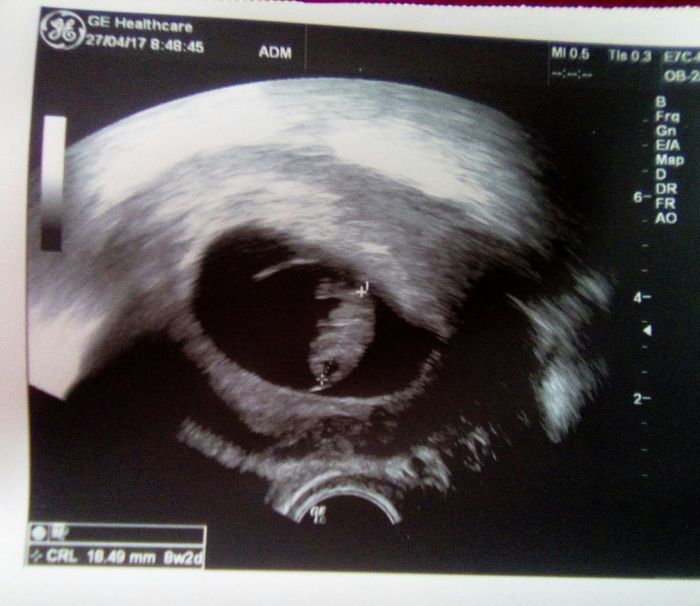

Dnes jsem se byla rozloučit v CARu, vše ok, srdíčko jsem viděla dnes i já, embryo odpovídá 8+2 :-) dostala jsem papíry pro mou doktorku.